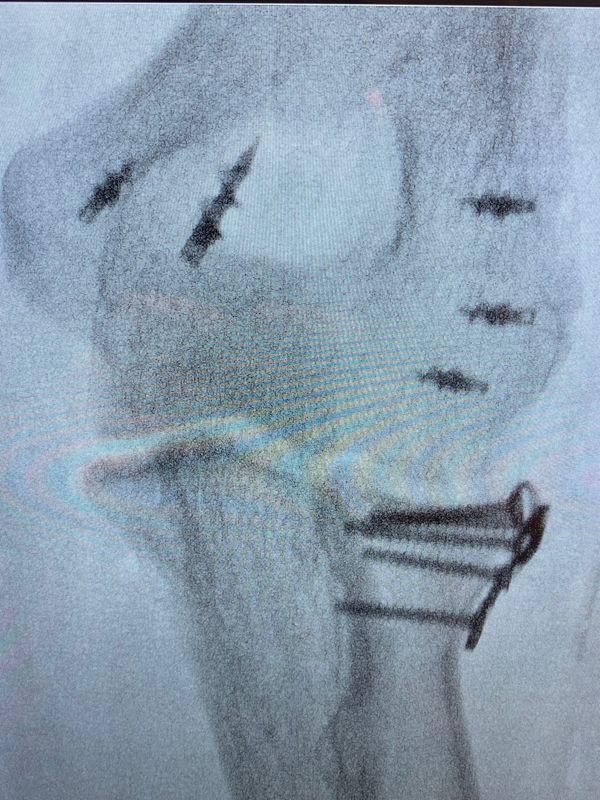

Dr ufuk nalbantoğlu. Percutaneous cannulated screw fixation in the treatment of distal radius fractures. özkan ufuk nalbantoğlu has international and national patents. Ufuk nalbantoğlu okan tok. Okan tok 90 530 246 56 75 90 535 412 12 05.

Ufuk nalbantoğlu orthopedics and traumatology at acibadem university atakent hospital speciality orthopedics. Dr öğr üyesi özkan ufuk nalbantoğlu. Arch orthop trauma surgery 2012. Gündoğan k aslan e.